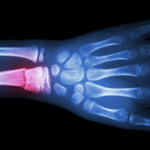

گرفتن تصاویر از مفصل خود با استفاده از :

اشعه ایکس، که می تواند از دست دادن فضای مفصل، آسیب استخوان، بازسازی استخوان و خار استخوان را نشان دهد. آسیب اولیه مفصل معمولاً در اشعه ایکس ظاهر نمی شود.